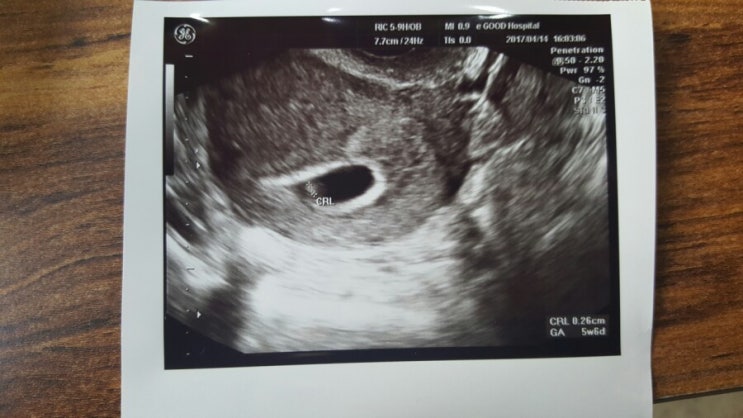

임신 6주 / 아기집 난황 확인 / 심장소리 / 임신6주차 증상 / 질초음파 /산모수첩

2017.04.14. (임신6주 마지막 생리 시작일 기준) 일주일 전에 병원갔다가 아기집만 확인하고 난황이 없어서...